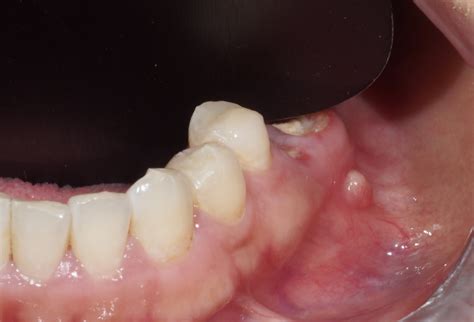

Llamamos fístula dental al canal que se origina desde la zona infectada de un diente hasta la superficie exterior de la encía. En ese canal se acaba depositando pus y, conforme se llena, se crea una protuberancia o grano próximo a las encías. Una fístula dental es una pequeña abertura o canal anormal que se forma en la encía o en la región cercana a la raíz de un diente infectado. El pasaje actúa como depósito de pus y a medida que se llena, se forma una pequeña protuberancia en forma de grano cerca de las encías.

La fístula al aparecer se presenta normalmente en la encía, en la cima superior del diente. Se trata, como bien indicábamos, de un bulto con pus producido por diferentes razones. Al principio, las encías se inflaman ligeramente y enrojecen. Con el tiempo, la fístula dental se llena de pus y aparece un dolor punzante. Si se aplica mucha presión, el pus drena hacia la cavidad oral. Cuando se forma la fístula dental, aún no causa dolor. Al principio, la zona afectada se hincha. Las encías se enrojecen y hay una sensación de tensión en el diente. A continuación, se forma una ampolla en la encía, encima o debajo del diente afectado, que se llena de pus a medida que avanza. La fístula dental empieza a palpitar y doler. Puede que incluso se te hinche la cara del lado afectado y te duela la cabeza.

- Abscesos dentales: La presencia de una fístula dental puede dar lugar a la formación de abscesos dentales. Un absceso dental es una acumulación de pus causada por una infección bacteriana en el tejido dental. En el caso de una fístula dental, el absceso puede manifestarse como una protuberancia roja y dolorosa en las encías cerca del diente afectado. Esta protuberancia puede estar acompañada de sensibilidad al tacto y al calor, así como de hinchazón en el área circundante.